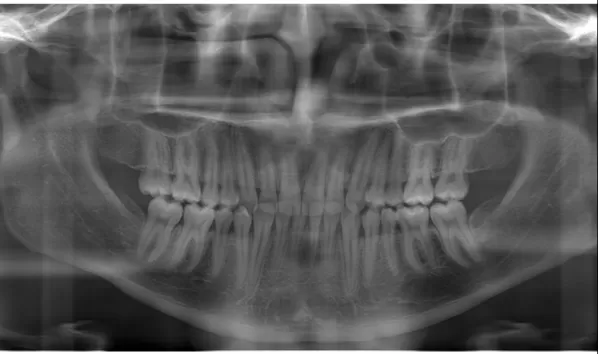

Rayons X avant le traitement

[Radiographie panoramique/Céphalogramme latéral]